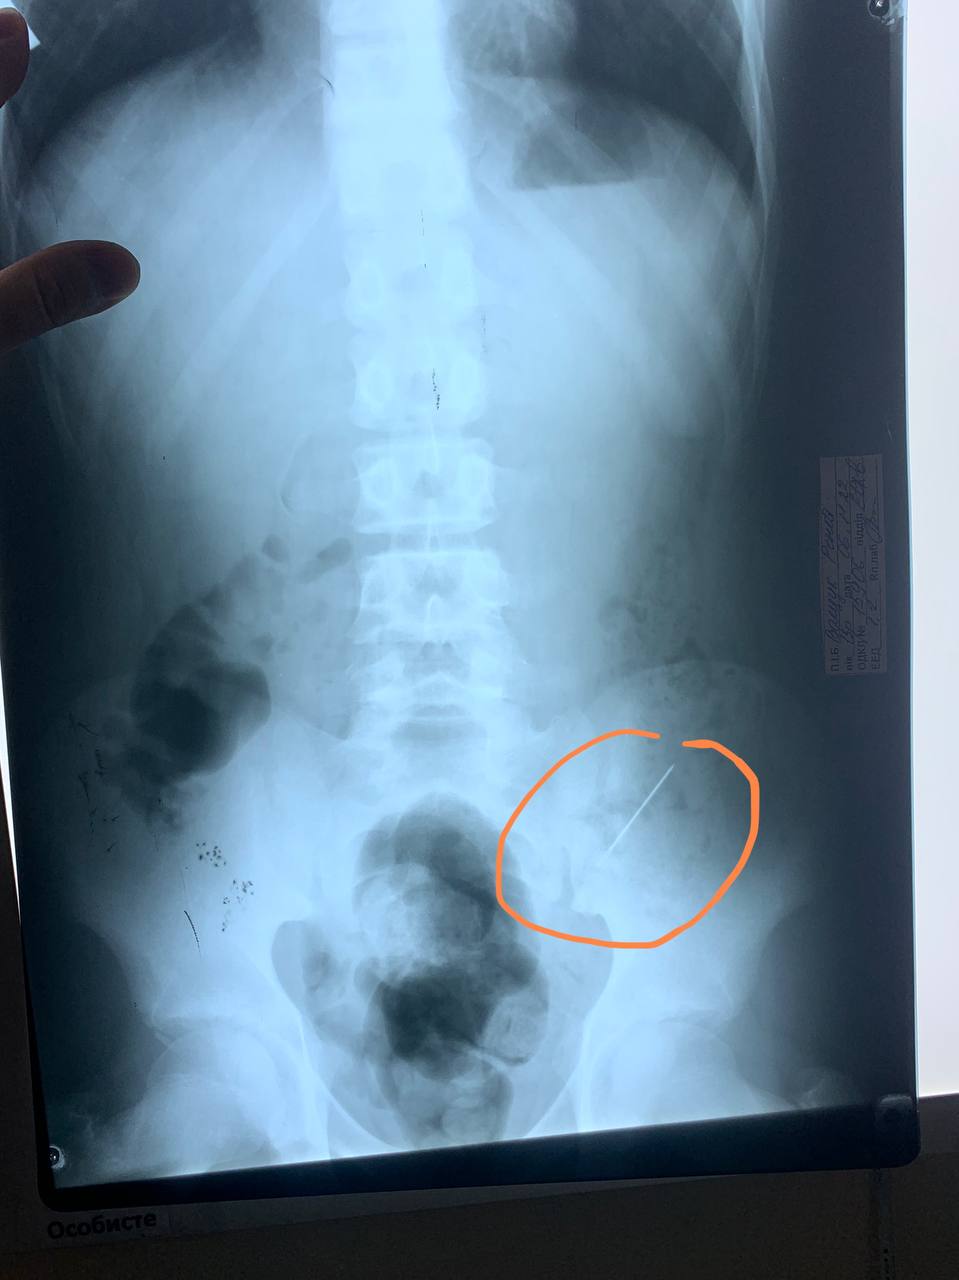

В Днепре врачи спасли 13-летнего мальчика, который по неосторожности проглотил иглу.

Врачи сделали рентген, который обнаружил иглу в организме. Медработники поделились, что было несколько вариантов развития ситуации - сделать гастроскопию или же оперативное вмешательство, если игла повредит внутренние органы.

Однако хирурги предусмотрели менее механический, однако и довольно рискованный вариант. Они постоянно наблюдали мальчика (делали пальпацию живота, повторные снимки), был шанс, что игла выйдет сама.

В случае с мальчиком на вторые сутки постоянного наблюдения врачами игла вышла естественным путем, не повредив ни одного органа.